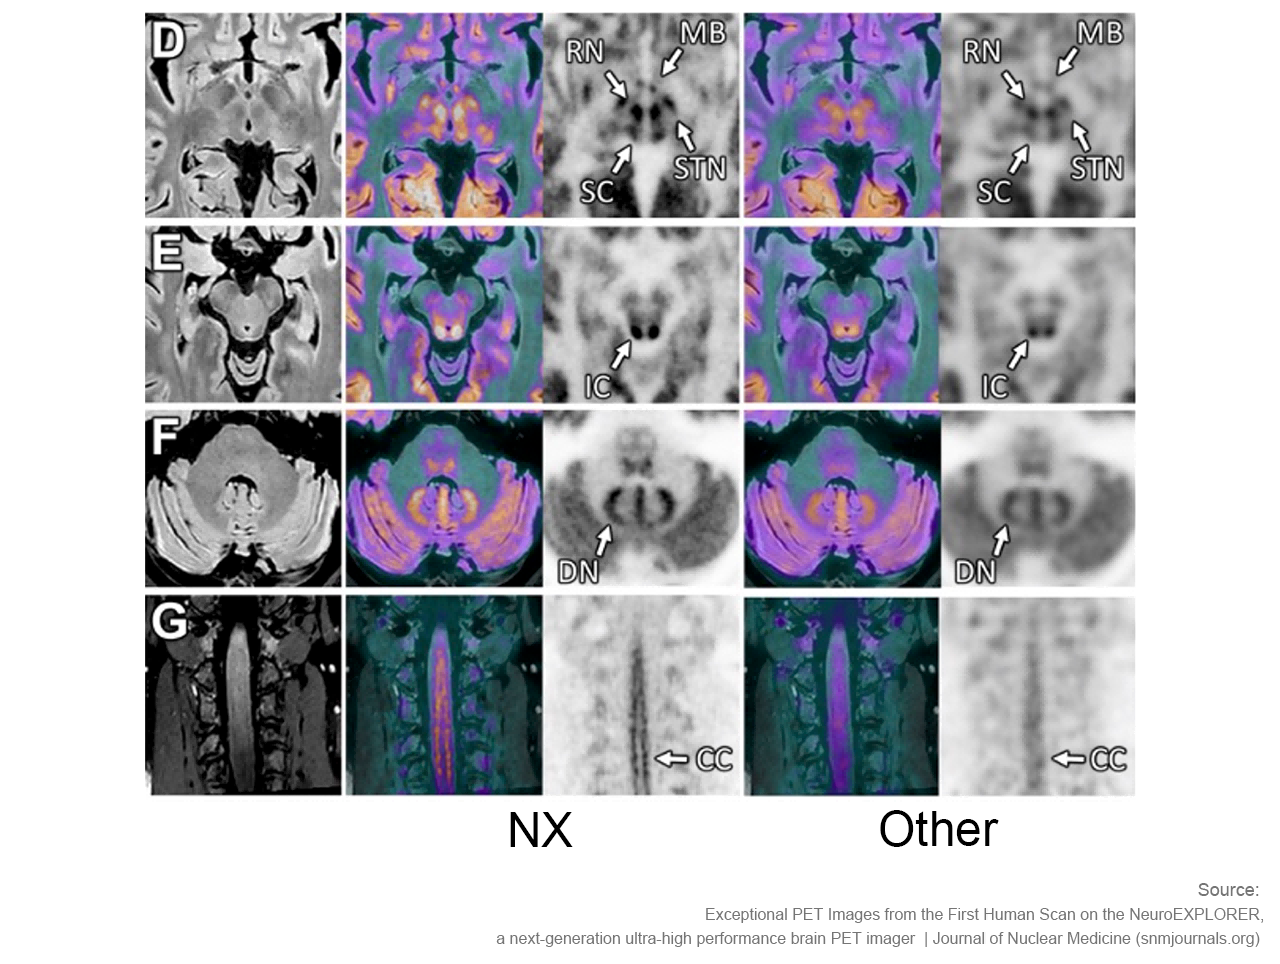

NeuroExplorer拥有基于NEMA NU 2-2018标准的超高灵敏度:46cps/kBq,同时配备着先进的时间飞行技术,进一步增强了NX的综合性能。

卓越空间分辨率 洞察大脑微观

小型探测器元件确保最精微的结构能被检测,甚至探查特定脑核中的神经递质运动。搭载1.5mm的有效空间分辨率,带来前所未见的解剖细节。

NeuroExplorer (NX)产出的脑部影像图与其他设备产出的脑部影像图对比

“从我们目前获取的图像来看,使用NeuroExplorer扫出的图像是世界上最好的,因此我们能够真正做到更好地缩小范围,聚焦更小的信号,观察大脑更为微末的区域,这为我们打开了新的窗口,去‘见所未见’。”Carson教授对NX的诞生和即将围绕其展开的一系列研究满怀期待,“有了NeuroExplorer这样强大的设备,我们步履不停,也正将迎来一个重要的突破,那就是和制药行业的合作。”